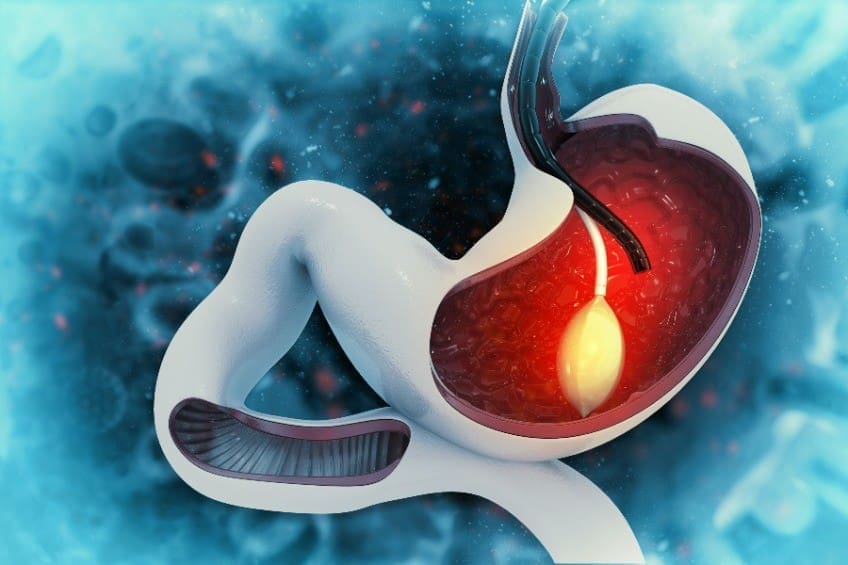

胃食道逆流門診

您是否常常覺得胸口灼熱感。火燒心胸口疼痛是一個不僅擾人也是相當重要的問題。尤其是中午飯後趴在桌上睡醒以後,或晚上平躺睡覺時,這種胸部的燒灼及沉悶的感覺更加嚴重,而這種症狀也容易反反覆覆發生。

在台灣,由於生活飲食習慣的西化,胃食道逆流疾病的病例也有明顯增加的趨勢,目前在消化道疾病中約佔10~20%的比例。

胃鏡、無痛式胃鏡

無痛式胃鏡是一種用於檢查胃部的醫療儀器,患者在檢查期間可能會感到有些不適,但通常不會有痛感。無痛式胃鏡可以用於診斷各種胃部問題,包括消化不良、潰瘍、癌症等。它是一種非常有效的檢查方式,可以幫助醫生精確診斷和治療胃部問題。